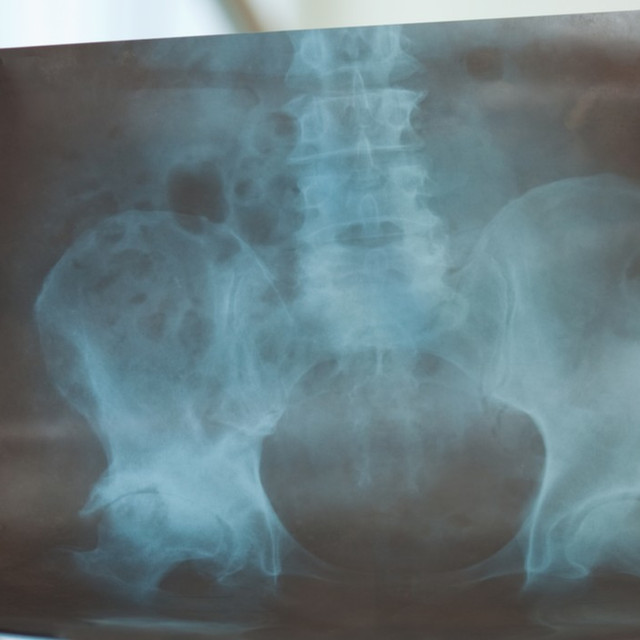

Bilateral Hip Arthroscopy Patients come from near and far for single Hip Arthroscopy Surgery Blog Hip arthroscopy is a minimally invasive surgery used to identify and repair damage in your hip. You can expect a recovery. February 9th 2017 i went into surgery to repair a torn labrum, and correct the fai in my right hip. Hip arthroscopy is a minimally invasive hip surgery using a small camera called an arthroscope. Along with the history. Hip Arthroscopy Surgery Blog.